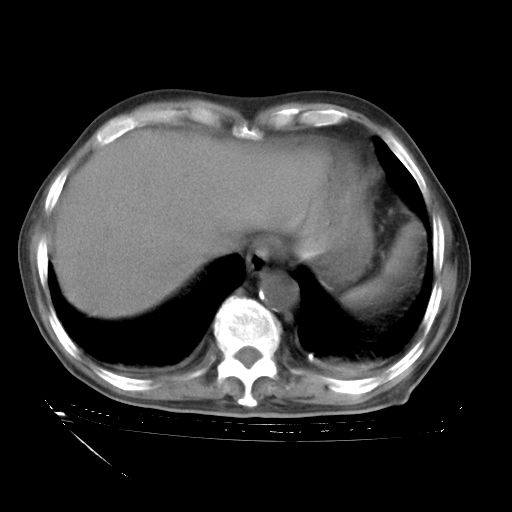

补充下:5月9日胸部CT:似乎已见双下肺胸腔积液了,鉴于目前有下肢水肿,肝功示:白蛋白低,应注意多浆膜腔积液(漏出液可能大?),需注意!

甲强龙80mg/日+抗结核治疗(异烟肼+利福霉素+乙胺丁醇)10天。复查肺部CT。

治疗10天肺部CT

94186 3 10.bmp

94186 3 11.bmp

94186 3 12.bmp

94186 3 13.bmp

94186 3 14.bmp

94186 3 15.bmp

94186 3 16.bmp

94186 3 17.bmp

94186 3 18.bmp

94186 3 19.bmp